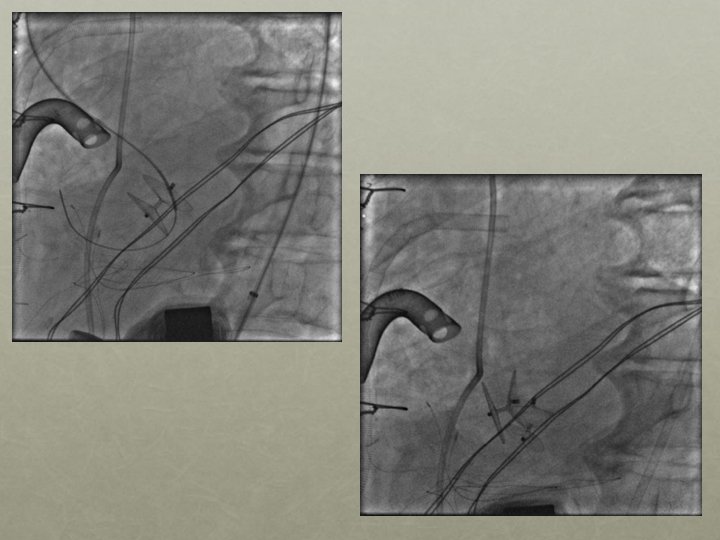

Amplatzer 25 mm Cribiform Septal Occluder

2 nd Septal Occluder Device Deployed